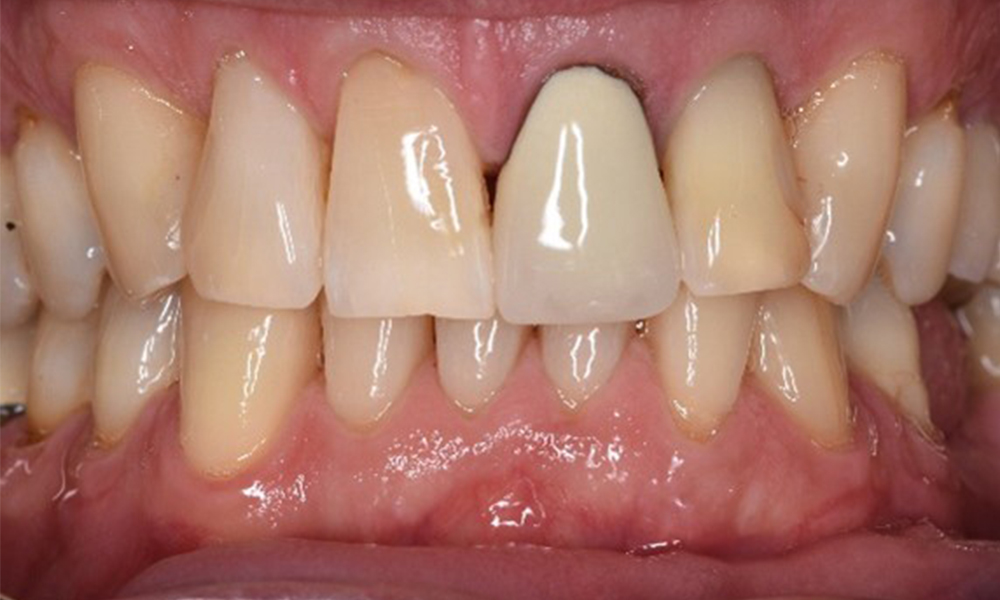

Pacient transplantat cu proliferări gingivale

Un pacient în vârstă de 71 de ani, cu transplant de rinichi și istoric de hipertonie (hipertensiune arterială) se prezintă în cabinet. Din cauza istoricului său medical, este necesară o medicație pe termen lung cu ciclosporină, pentru a suprima sistemul imunitar, precum și amlodipină pentru a reduce tensiunea arterială. Pacientul raportează, de asemenea, gingii sensibile și sângerânde. Din punct de vedere al sănătății orale, pacientul are lucrări dentare, o edentație de opt dinți, creștere gingivală pronunțată și parodontoză de gradul B, stadiul II, cu pungi active și carii radiculare inițiale la dintele 22. Evaluarea riscului de carie determină un risc moderat de carie (API 60). Se pot stabili următoarele recomandări de tratament pentru ședința de profilaxie. mai multe